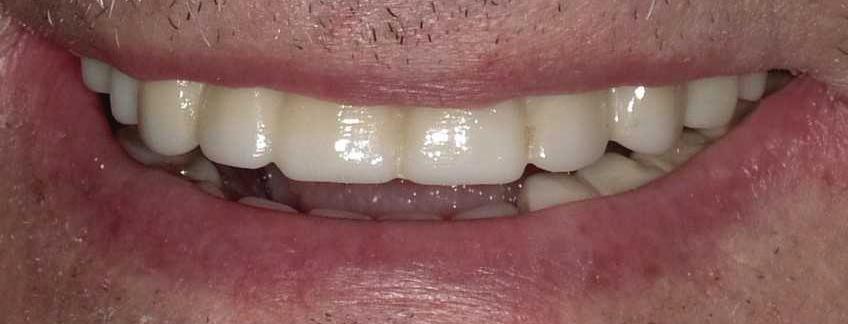

Can just four implants replace all of the teeth on the top or the bottom of your mouth? Thanks to advances in dental implant technology, that answer is a resounding yes.

Believe it or not, tooth loss is extremely common among adults, especially as we age. In fact, more than 35 million people in America are missing all of their upper and/or lower teeth. Rather than living with the discomfort and hassles of dentures, many people are opting for what is called “all-onfour” dental implant restoration.

All-On-Four: One Full Arch Of Teeth, Four Dental Implants

A Reason To Smile Again

able technique for replacing teeth, you should first understand what a dental implant is. An implant is a small titanium screw that fits inside your jawbone and replaces the root-part of a missing tooth. Minor surgery is required to insert the implants. Once the implant is in place, a crown is attached to give you a highly realistic-looking and functional prosthetic tooth.

Here’s where it gets really interesting: You do not need a dental implant for each and every one of your missing teeth. All you need is four precisely placed implants on the top of your mouth, and four on the bottom, to restore your full smile. That’s the beauty of the all-on-four. And because the implant is made of titanium, it has the unique ability to fuse to living bone and function as part of it. So eventually, the dental implant becomes part of the jawbone and serves as a strong, long-lasting foundation for your new teeth.

Besides ensuring that your implants are permanently fixed in place,

Missing Teeth or Tired of Wearing Dentures?

Thanks to advances in dental implant technology, just four implants can replace all of the teeth on the top or the bottom of your mouth.

this bone fusion has another important benefit: it prevents future bone loss in the jaw. This helps to maintain a more youthful facial structure – and better oral health. But perhaps the biggest surprise about the all-on-four is how quickly it can transform your life.

What’s The All-On-Four Dental Implant Procedure Like?

It can be scary to get implants for the first time. Most of that fear is probably due to the uncertainty, so here is the step-by-step process for getting an All-On-Four dental implant.

First, your dentist will want to make sure your comfortable, so either local or general anesthesia will be administered.

Second, the dentist or surgeon will prepare your mouth for the implants, which involves removing your remaining teeth that are failing. They will then remove any diseased or infected tissue from your jaw and gums.

Next, they will begin the implantation process. This means they will

insert the titanium screws into your jawbone. Most likely, they will place two implants toward the front of your mouth and two towards the back of your mouth so the “anchors” can evenly bare the force of the denture.

After the implants have been placed, they will thoroughly clean the surgical sites and suturing all the incisions. Then you’ll be taken to a recovery room where you can relax and take time to wake up from the anesthesia.

How Do You Know If The All-On-Four Procedure Is The Right Option For You?

At your All-On-Four consultation, you’ll receive a 3D CT Scan. This scan will help determine if you need implants and assist your doctors in creating your treatment plan. So if you want to learn more about dental implants, simply schedule a consultation with an All-On-Four provider. It’s the best way to find out how dental implants can change your life.